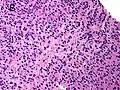

Gleason score 7 (3+4) with minor component of cribriform glands